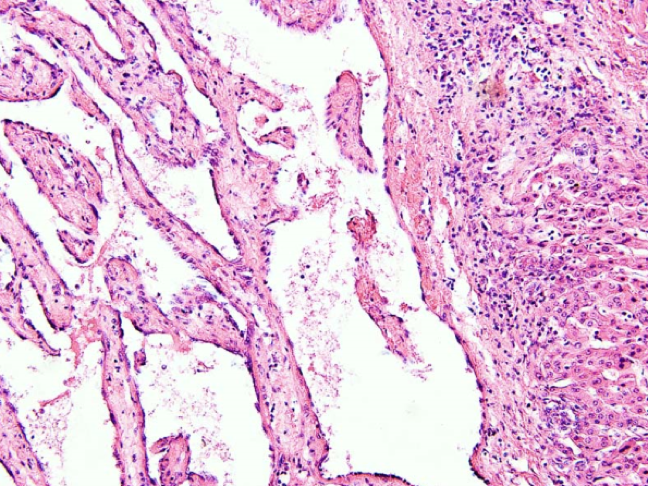

5.血管肉瘤(hemangiosarcoma)

血管肉瘤起源于血管内皮细胞,有时又称恶性血管内皮瘤,可发生在各器官和软组织。发生于软组织者多见于皮肤,尤以头面部为多见。

血管肉瘤一般恶性程度较高,常在局部淋巴结、肝、肺和骨等处形成转。

(2)镜下观

分化好者瘤组织形成大小不一,形状不规则管腔,肿瘤性血管内皮细胞有不同程度异型性,可见核分裂像;分化差者瘤细胞常呈团片状增生,血管腔可不明显,瘤细胞异型性明显,核分裂像多见。免疫组化显示第八因子和CD34阳性。

血管肉瘤:瘤细胞异性型非常显著,可以看见血管腔。